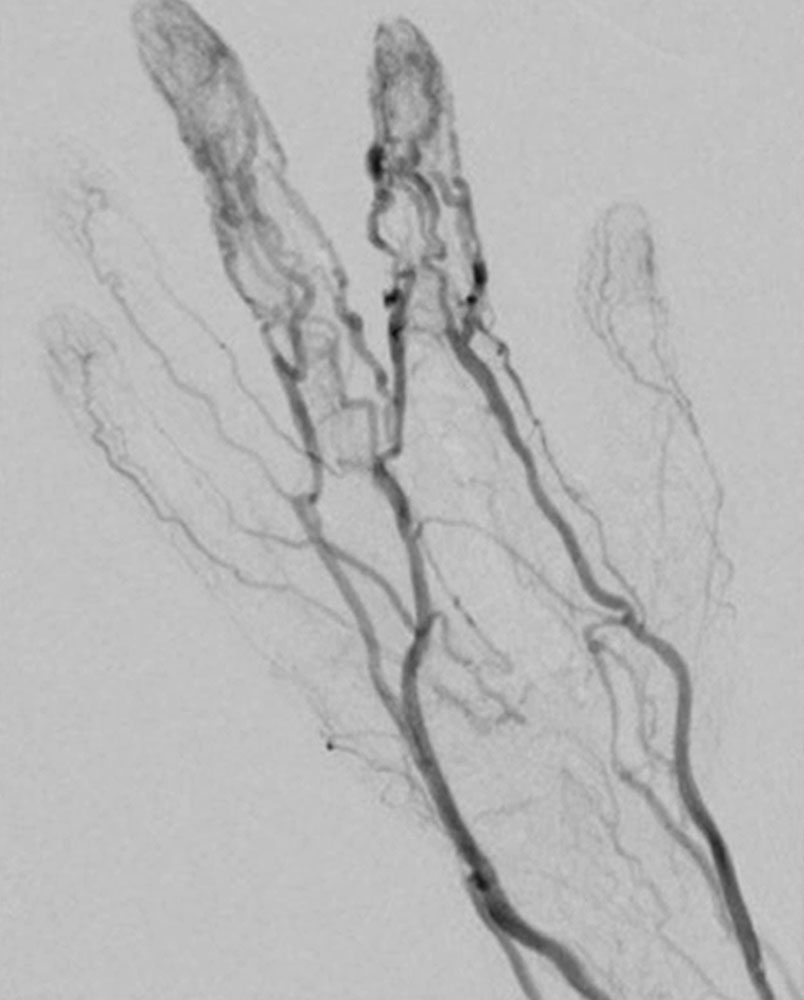

In most cases, catheter angiography is only performed as part of a minimally invasive treatment. The arteries supplying the nidus are often twisted, dilated and sometimes aneurysmally dilated. As a result of the arteriovenous shunt connections, there is immediate, early contrast filling of the dilated veins.

Peripheral arteriovenous malformations can be classified according to their angiographic anatomy, particularly their venous outflow.

Unlike venous malformations, there is characteristically no extensive contrast agent accumulation or contrast agent stasis in the form of "pooling". A so-called “blush” in the sense of a very fine fistulous nidus may appear at a very early stage of an arteriovenous malformation, for example in children, and this appears similar to a vascular tumor without a space-occupying mass.